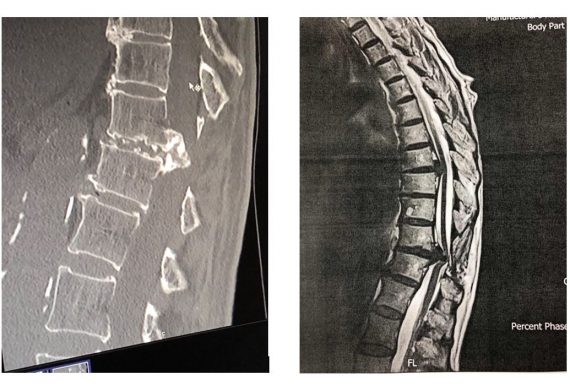

Με την πάροδο του χρόνου οι μεσοσπονδύλιοι δίσκοι μπορεί να υποστούν φθορά και να προβάλουν προς τα πίσω, πιέζοντας το νωτιαίο μυελό και τα νεύρα. Μάλιστα, συχνά, στη θωρακική μοίρα οι δισκοκήλες είναι επασβεστωμένες ή συνοδεύονται από μεγάλα οστεόφυτα (Εικόνα 1)